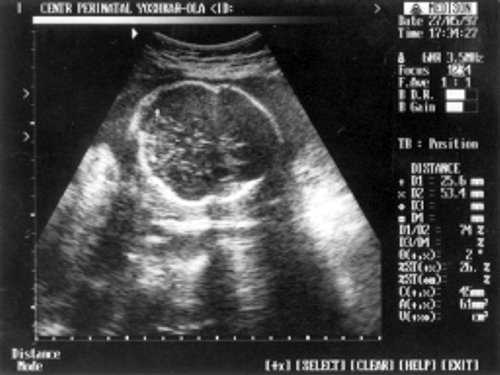

МРМ (межполушарный размер мозжечка) = 25,6 мм - 23,5-24 нед. (рис. 1)

- МРМ (межполушарный размер мозжечка) = 25,6 мм - 23,5-24 нед. (рис. 1)

Рис. 1. УЗИ плода - голова.